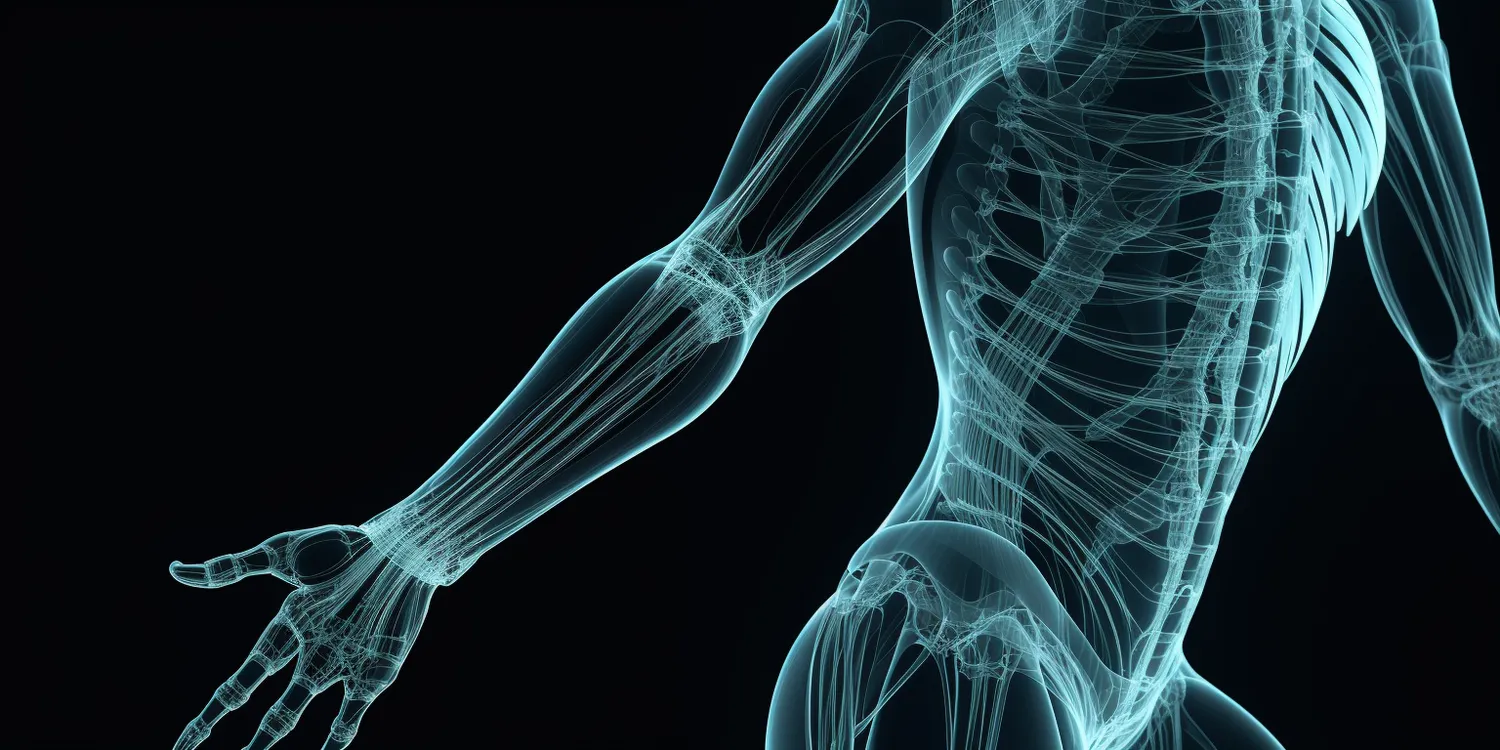

Rehabilitacja to proces, który ma na celu przywrócenie pacjentowi pełnej sprawności fizycznej oraz psychicznej po urazach, operacjach czy chorobach. Warto zrozumieć, że rehabilitacja nie jest jedynie zestawem ćwiczeń, ale kompleksowym podejściem do zdrowia pacjenta. Obejmuje ona różnorodne metody terapeutyczne, które są dostosowane do indywidualnych potrzeb każdej osoby. W zależności od rodzaju schorzenia, rehabilitacja może obejmować fizjoterapię, terapię zajęciową, logopedię czy psychoterapię. Kluczowym elementem rehabilitacji jest współpraca z zespołem specjalistów, którzy wspólnie opracowują plan terapeutyczny. Ważne jest również zaangażowanie samego pacjenta w proces leczenia, ponieważ jego motywacja i determinacja mają ogromny wpływ na efekty terapii. Warto również pamiętać, że rehabilitacja to nie tylko działania podejmowane w placówkach medycznych, ale także ćwiczenia i aktywności wykonywane w domu, które mogą wspierać proces zdrowienia.

W rehabilitacji stosuje się wiele różnych metod, które są dostosowane do potrzeb pacjentów oraz rodzaju ich schorzeń. Jedną z najpopularniejszych metod jest fizjoterapia, która obejmuje różnorodne techniki manualne oraz ćwiczenia mające na celu poprawę ruchomości stawów i siły mięśniowej. Fizjoterapeuci często wykorzystują także urządzenia takie jak ultradźwięki czy elektroterapia, które wspomagają proces gojenia tkanek. Inną istotną formą rehabilitacji jest terapia zajęciowa, która koncentruje się na przywracaniu zdolności do wykonywania codziennych czynności. Terapeuci zajęciowi pomagają pacjentom w adaptacji do nowych warunków życia po urazach lub chorobach przewlekłych. Logopedia to kolejna ważna dziedzina rehabilitacji, szczególnie dla osób po udarach mózgu czy z zaburzeniami mowy. Specjaliści w tej dziedzinie pracują nad poprawą zdolności komunikacyjnych pacjentów. Wreszcie psychoterapia może być niezbędna dla osób borykających się z problemami emocjonalnymi związanymi z ich stanem zdrowia.

Rehabilitacja odgrywa kluczową rolę w procesie powrotu do zdrowia po urazach czy chorobach przewlekłych. Jej celem jest nie tylko przywrócenie sprawności fizycznej, ale także poprawa jakości życia pacjentów. Dzięki odpowiednio dobranym ćwiczeniom i terapiom możliwe jest zmniejszenie bólu oraz poprawa funkcji ruchowych, co pozwala na szybszy powrót do codziennych aktywności. Rehabilitacja ma również znaczenie psychologiczne; pacjenci często odczuwają większą motywację i nadzieję na poprawę swojego stanu zdrowia dzięki regularnym spotkaniom z terapeutami oraz postępom w leczeniu. Co więcej, rehabilitacja może pomóc w zapobieganiu nawrotom chorób oraz utrzymaniu osiągniętej sprawności przez dłuższy czas. Osoby uczestniczące w programach rehabilitacyjnych uczą się także technik radzenia sobie ze stresem oraz zarządzania swoim zdrowiem na co dzień.

Rehabilitacja jest niezbędna w przypadku wielu różnych schorzeń, które mogą wpływać na sprawność fizyczną i psychologiczną pacjentów. Wśród najczęstszych problemów zdrowotnych, które wymagają interwencji rehabilitacyjnej, znajdują się urazy ortopedyczne, takie jak złamania czy skręcenia stawów. Po takich kontuzjach rehabilitacja ma na celu przywrócenie pełnej funkcji kończyny oraz zmniejszenie bólu. Kolejną grupą schorzeń są choroby neurologiczne, takie jak udar mózgu czy stwardnienie rozsiane, które mogą prowadzić do osłabienia siły mięśniowej oraz zaburzeń koordynacji. Rehabilitacja neurologiczna koncentruje się na poprawie zdolności ruchowych oraz funkcji poznawczych pacjentów. Warto również wspomnieć o chorobach układu oddechowego, takich jak przewlekła obturacyjna choroba płuc (POChP), gdzie rehabilitacja oddechowa może pomóc w poprawie wydolności organizmu oraz jakości życia. Osoby z problemami kardiologicznymi, takimi jak po zawale serca, również często korzystają z programów rehabilitacyjnych, które mają na celu poprawę kondycji sercowo-naczyniowej.

Korzyści płynące z rehabilitacji są wieloaspektowe i mają znaczący wpływ na jakość życia pacjentów. Przede wszystkim rehabilitacja pozwala na przywrócenie sprawności fizycznej, co umożliwia pacjentom powrót do codziennych aktywności oraz pracy zawodowej. Dzięki odpowiednim ćwiczeniom i terapiom można zredukować ból oraz poprawić zakres ruchu, co jest szczególnie istotne w przypadku osób po urazach ortopedycznych czy operacjach. Rehabilitacja ma także pozytywny wpływ na zdrowie psychiczne; pacjenci często odczuwają większą motywację do działania oraz poprawę nastroju dzięki regularnym spotkaniom z terapeutami oraz postępom w leczeniu. Współpraca z zespołem specjalistów daje pacjentom poczucie wsparcia i bezpieczeństwa, co sprzyja ich zaangażowaniu w proces terapeutyczny. Ponadto rehabilitacja może pomóc w zapobieganiu nawrotom chorób oraz utrzymaniu osiągniętej sprawności przez dłuższy czas. Osoby uczestniczące w programach rehabilitacyjnych uczą się także technik radzenia sobie ze stresem oraz zarządzania swoim zdrowiem na co dzień, co przekłada się na lepszą jakość życia.